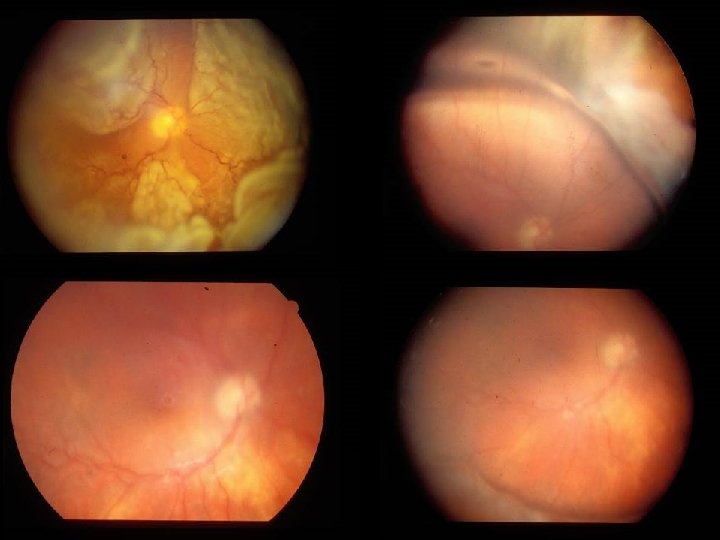

ESAMI DIAGNOSTICI OFTALMOSCOPIA E BIOMICROSCOPIA F A G (EV. ICG) ECOGRAFIA OCT ESAMI ELETTROFUNZIONALI

Classificazione delle alterazione retiniche nel diabete (Scuderi G. 1960) Forme pure Vasculopatia lieve Microaneurismi e emorragie puntiformi Retinite puntata A tipo prevalentemente emorragico A tipo prevalentemente degenerativo Vasculopatia marcata Gravissime emorragie retiniche e preretiniche con serie lesioni vasali specie venose Vasculopatia grave Invasione emorragica del vitreo Trombosi venosa diabetica Forme spurie od ibride Retinopatia diabetica-arteriosclerotica Retinopatia diabetica nefritica (iperazotemica-albuminurica gravidica) Retinopatia proliferante

CLASSIFICAZIONE RETINOPATIA DIABETICA NON PROLIFERANTE PROLIFERANTE AIRLIE HOUSE CLASSIFICATION MODIFICATA DA EARLY TREATMENT DIABETIC RETINOPATHY STUDY GROUP 1991